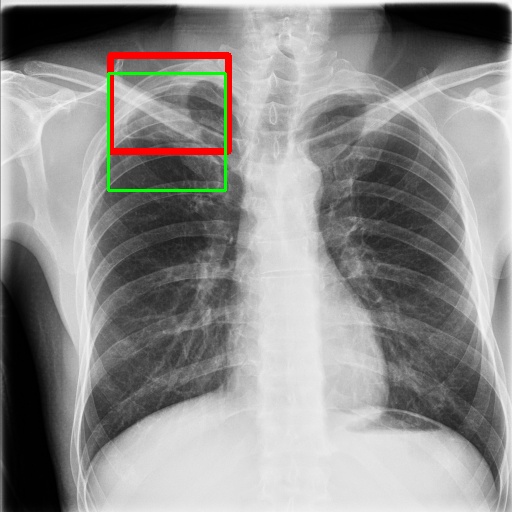

6.4 Visualization

To gain insights into the learning process of deep neural networks on CXR images, we visualize the feature map of SymFormer w/ RetinaNet at a scale of . To achieve this, we employ principal component analysis (PCA) to reduce the channels of the feature map to a single channel. The resulting single-channel map is then converted into a heat map for visualization purposes. The visualization of the learned features, along with the corresponding detection results, are presented in Fig. 6. Upon analysis, we observe that the visualization of healthy cases exhibits irregular feature patterns, indicating the absence of significant abnormalities. In contrast, the visualization of sick but non-TB cases displayed some discernible highlights, potentially representing the presence of lesions. For TB cases, the highlights in the visualization map align well with the annotated TB infection areas, thereby indicating the effectiveness of the proposed SymFormer in learning deep features for TB area detection. Furthermore, in Fig. 7, we offer qualitative comparisons between the proposed SymFormer and the baseline models for TB infection area detection. As evident, SymFormer consistently delivers superior qualitative detection results.